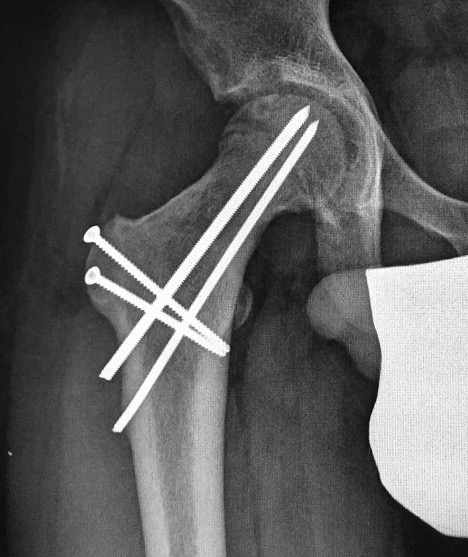

Subtrochanteric fracture

Subtrochanteric fracture likely causes by multiple drill holes / attempts

Cause

Too low screw entry

Multiple drill holes to get correct entry

Management

Intramedullary nail